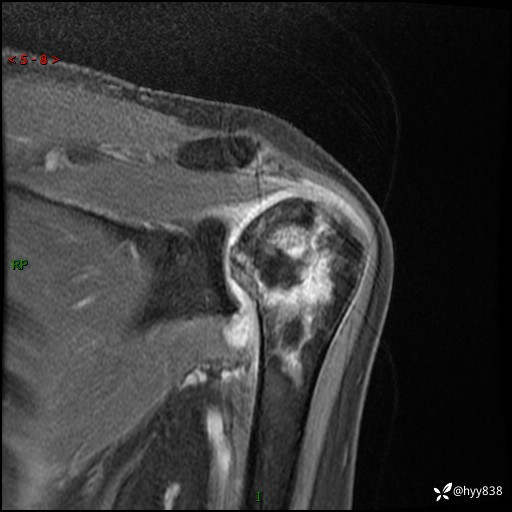

肱骨正侧位片

肱骨MRI平扫(axi T1WI+cor T2WI-fs)+CE-fs(COR+SAG)